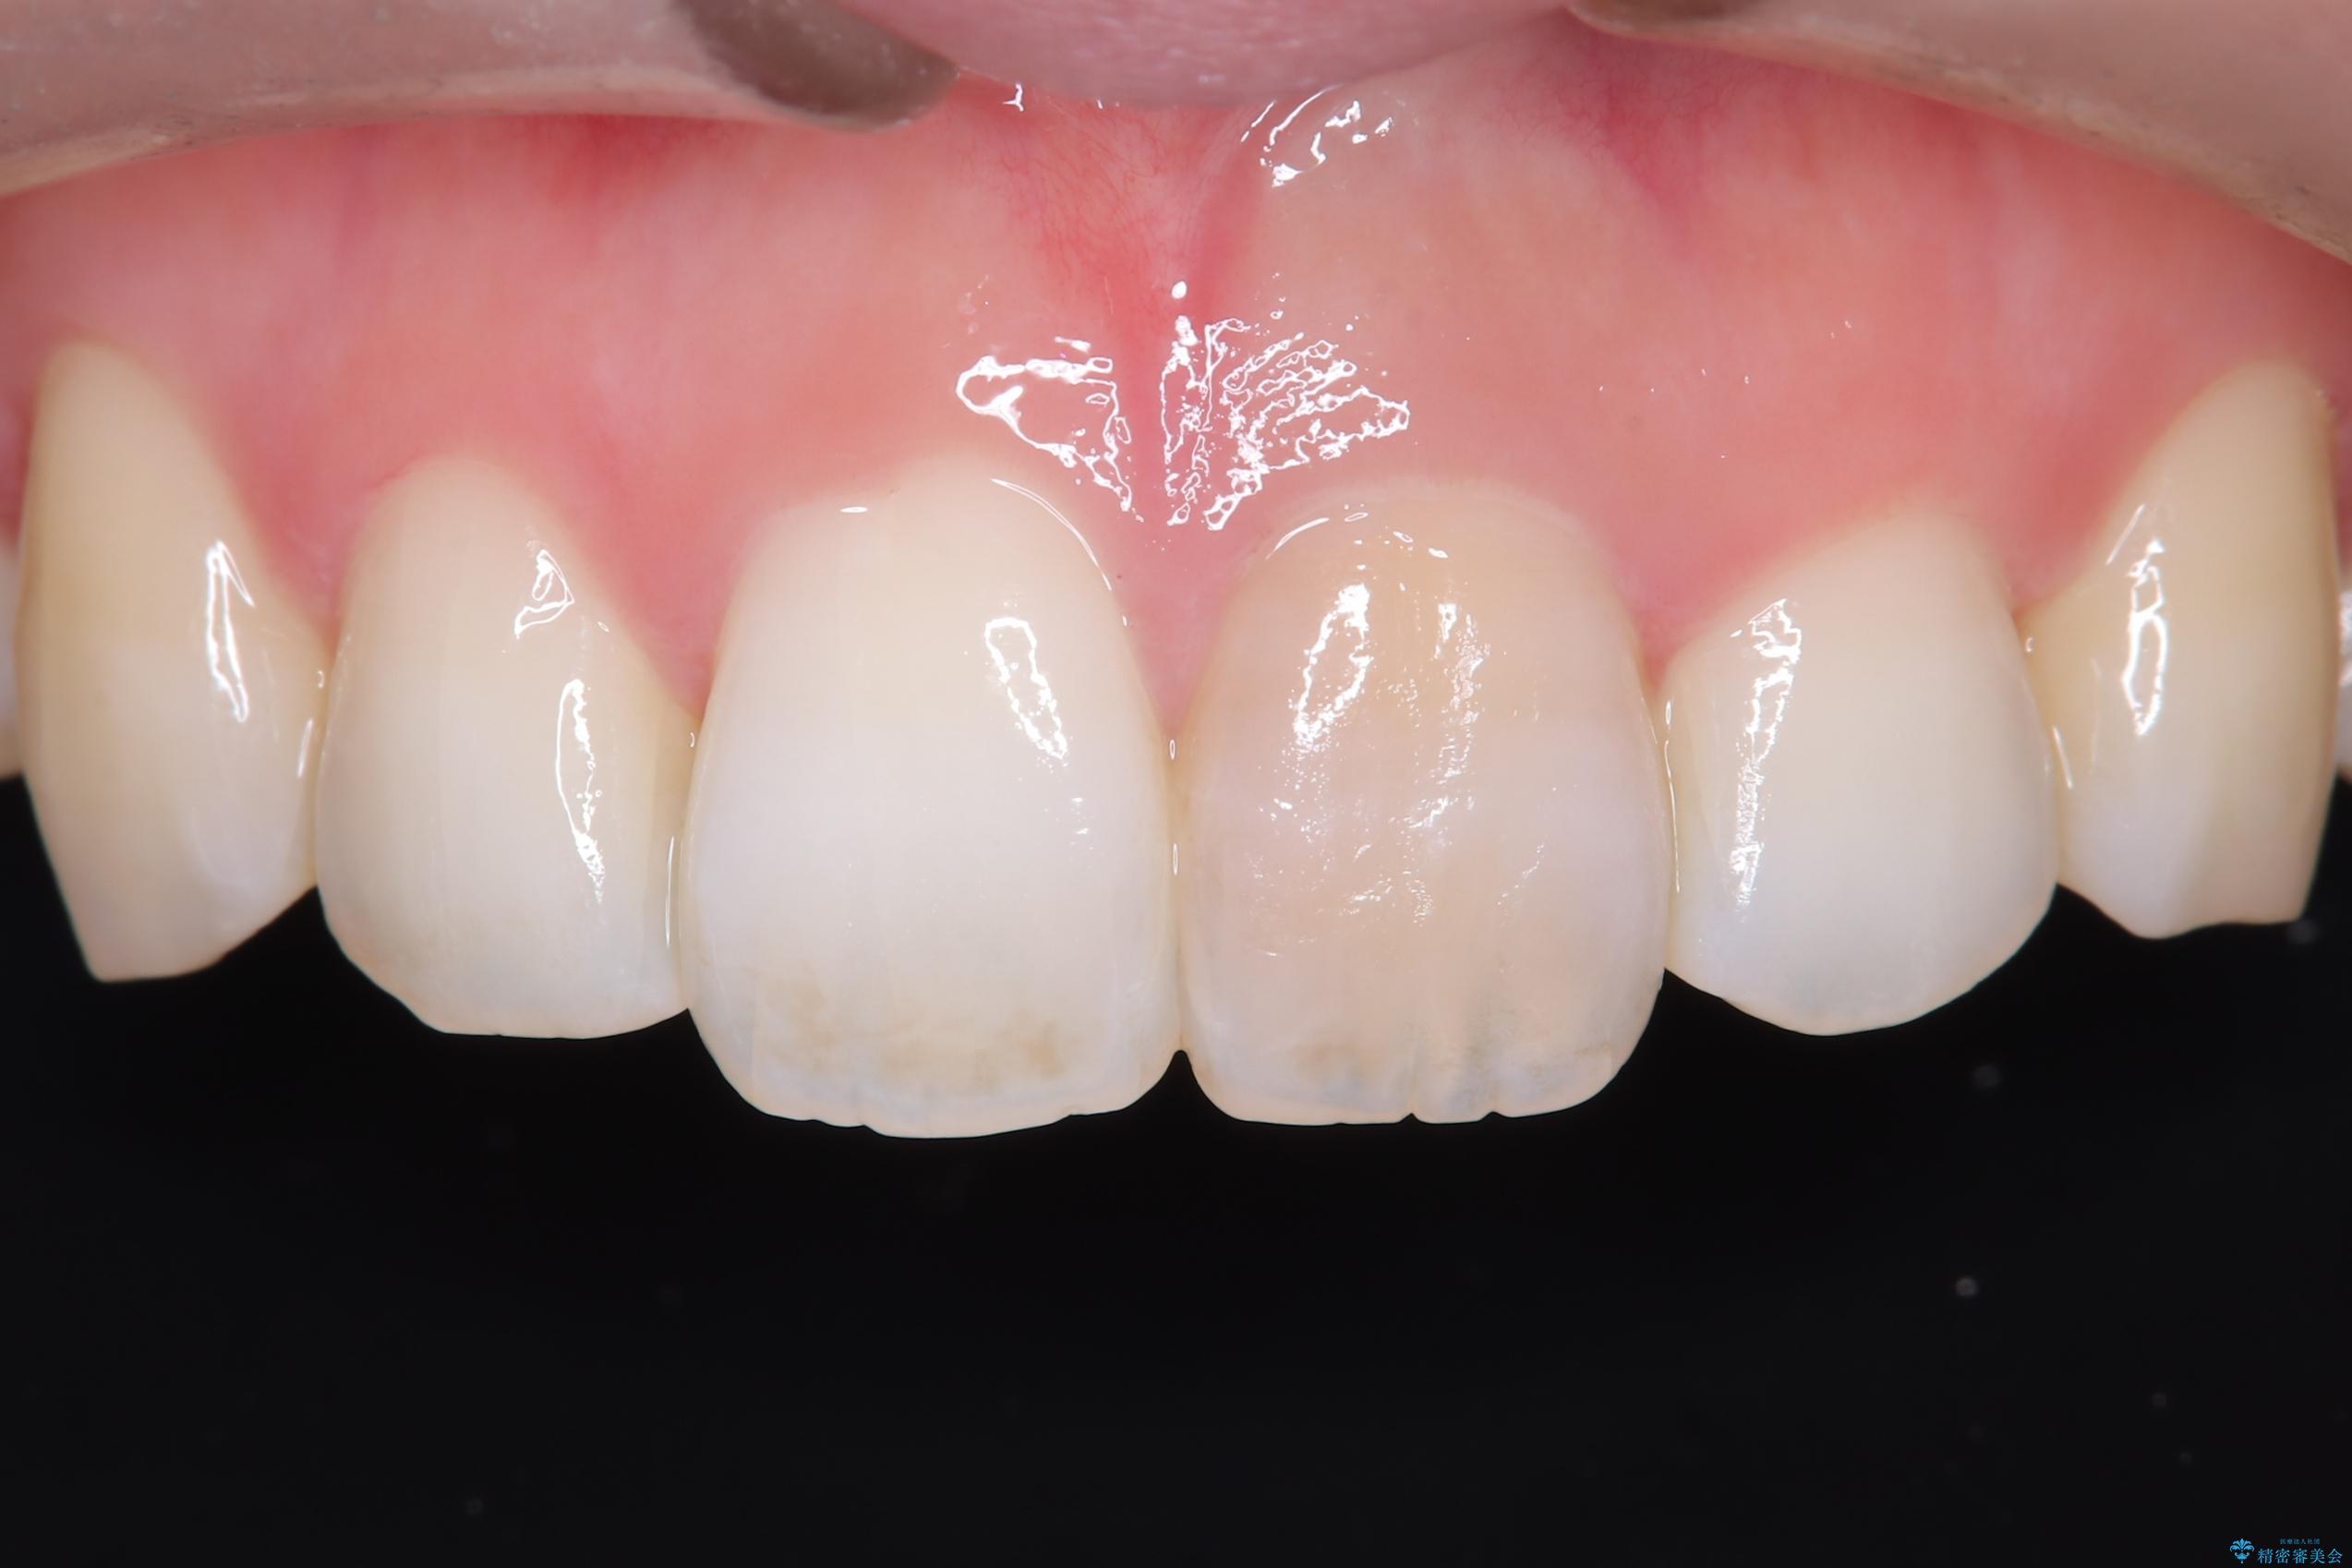

- 「以前、他院で神経を取った前歯がだんだん黒ずんできた」という見た目の改善を主訴にご来院されました。 診査の結果、神経を取り除いた後の歯(失活歯)特有の変色が起きており、さらに根の先端にわずかな影が見られたため、内部で感染が起きている可能性がありました。

そこで、まずは土台を外して根の内部をきれいにする再根管治療を行い、基礎をやり直した上で、透明感の高いオールセラミッククラウンで被せ直す治療計画を立案。単に白くするだけでなく、再発を防ぎ、長期的に美しい状態を保つことを目指しました。

精密な再根管治療: 古い充填材を除去し、歯科用顕微鏡を用いて根管内を徹底的に清掃・殺菌しました。根の先まで確実に薬剤を詰め直すことで、将来的な根尖病変(根の先の膿)のリスクを最小限に抑えました。

オールセラミッククラウンによる修復: 最終的な被せ物には、一切の金属を使用しないオールセラミックを選択。隣の天然歯と色調や透明感を精密に合わせることで、どこを治療したかわからないほど自然な仕上がりとなりました。